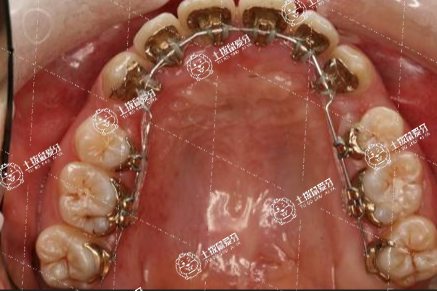

口腔健康可以說是全身健康的重要組成部分,不管是成年人還是未成人,只要有牙齒畸形問題,都不能忽視,需要及時(shí)科學(xué)的進(jìn)行牙齒矯正。對于深覆合牙友們來說,也需要在最佳時(shí)間進(jìn)行矯正,牙齒深覆合矯正的最佳年齡是什么?一起來了解一下。

牙齒深覆合矯正沒有年齡限制的。但是在一定年齡段是最佳的牙齒深覆合矯正階段,比如大部分都是在青春期左右進(jìn)行治療是最佳的年齡段。因?yàn)樵谶@個(gè)階段,由于患者是屬于快速生長期,無論是組織改造,還是代謝速度都非???,而且牙齒移動(dòng)也比較快,所以在這個(gè)時(shí)期進(jìn)行矯正效果會比較明顯。所以一定不要錯(cuò)過最佳的治療時(shí)間,以免增大治療難度。

深覆合矯正的最佳年齡大概在11歲到13歲左右,并不能夠具體完全的確定。如果牙齒出現(xiàn)了深負(fù)荷的情況,通過矯正的方式能夠達(dá)到改善的效果,而且在矯正之后也可以使牙齒排列整齊,并且在11歲到13歲左右,基本牙齒已經(jīng)更換完畢,在矯正的時(shí)候也能夠較快的改善,還能夠使牙齒快速的恢復(fù)到正常的位置。